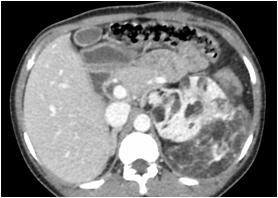

Radiological imaging was done in all the cases. USG findings revealed solitary masses in 45 cases (80.35%) and diffuse masses in 11 (19.64%). Solitary masses were around 45 in number out of which 30 were diagnosed as HCC. Right lobe had around 30 (66.7%) whereas left lobe had 15 (33.33%) masses respectively. Maximum (SOL’s) observed showed hyper-echogenicity present in 43 cases (76.78%). Heterogenous echotexture was observed in 6 cases (10.71%) (Fig 1).

CT scan was done in two patients which showed multiple well defined hyperdense lesions and hypodense lesions in another patient. Cyto-radiological correlation of hepatic masses was seen in 94% cases (Fig 2).

Fig 1 — USG liver showing well defined heteroechoic lesion in left lobe

Fig 2 — CT liver showing multiple enhancing focal hepatic lesions suggestive of metastasis